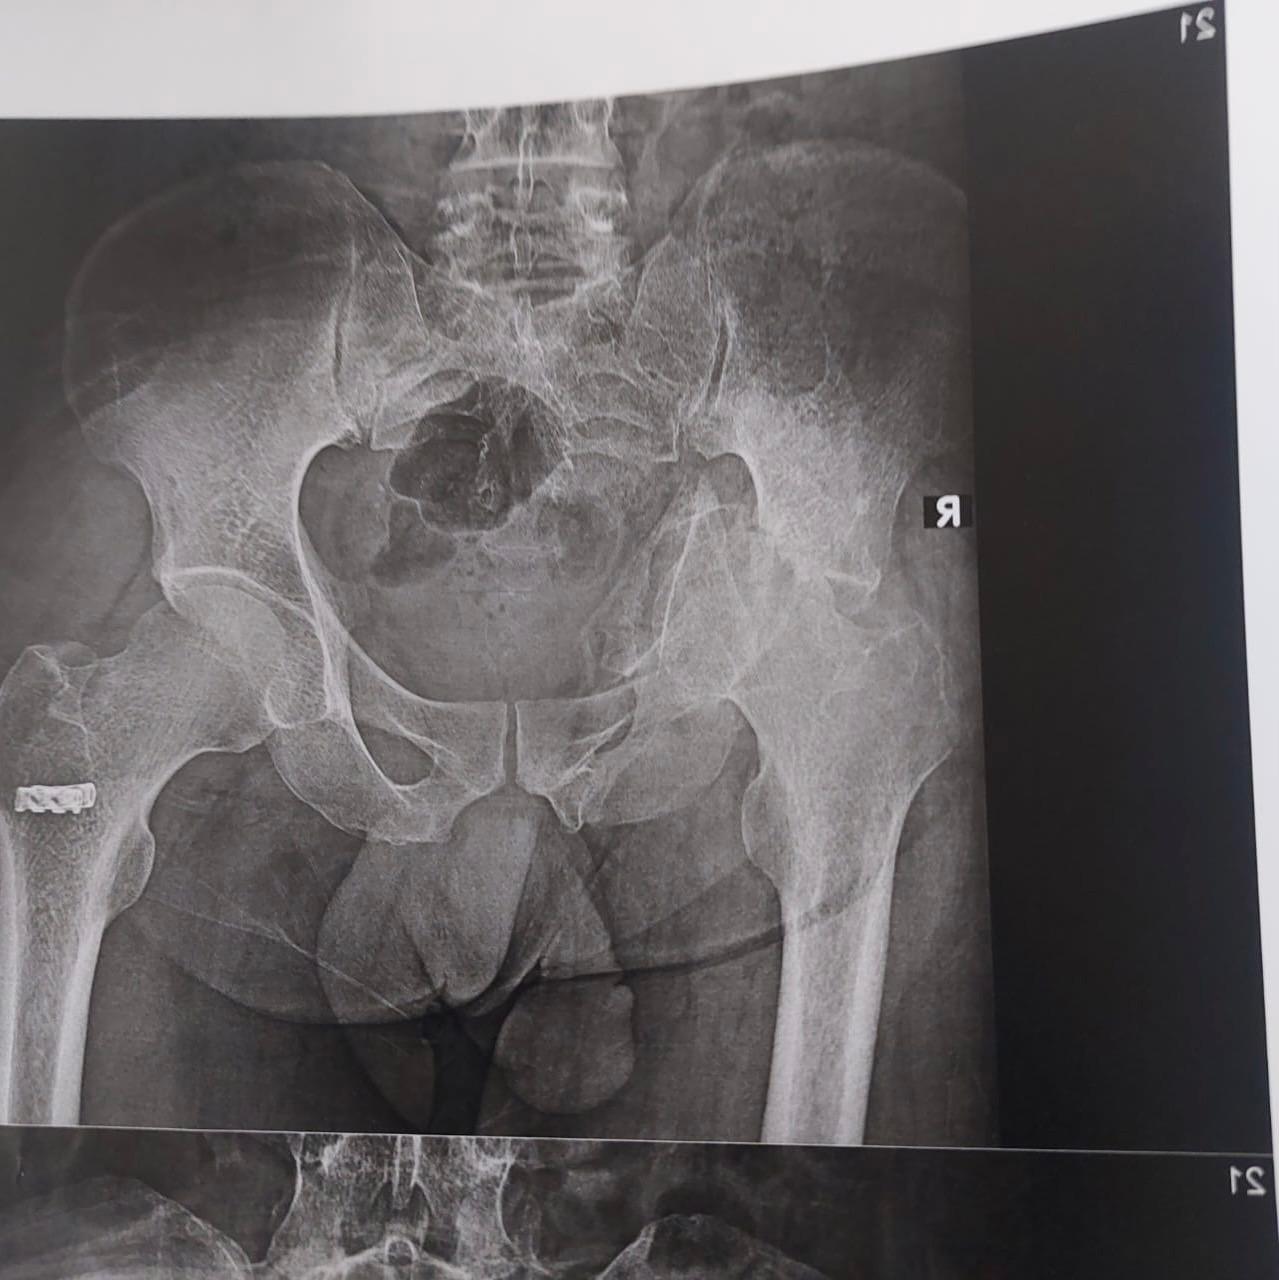

من جانبه قال الدكتور مجدي القاضي عميد كلية الطب بجامعة سوهاج انه تم تقييم الحالة الصحية لأحد المرضي الأشقاء من أهالى غزة، ويبلغ من العمر 41 عاما ويعانى من خلع بمفصل الحوض منذ ٦ شهور، وعلى الفور تم إجراء العملية الجراحية للمريض وتركيب مفصل حوض كامل، مضيفًا أن ادارة المستشفي تولي اهتمام كبير ورعاية مستمرة لجميع مصابي غزة منذ ان وطأت أقدامهم المستشفي الجامعي، وذلك تنفيذًا لتوجيهات الدكتور حسان النعماني رئيس الجامعة واهتمامه البالغ بمتابعته المستمرة لمستوي التحسن لحالتهم الصحية.

وقال الدكتور عبدالرحمن الشيخ رئيس قسم العظام بمستشفى سوهاج الجامعى انه تم استقبال المريض بقسم العظام وإجراء الفحوصات والتحاليل المخبرية والأشعات اللازمة وعلي الفور تم تشكيل الفريق الطبي المعالج الذي اجري العملية الجراحية ببراعة كبيرة، حيث بلغت تكلفة المفصل ٨٥ الف جنيه كتبرع من قسم العظام، موضحًا ان الفريق الطبي تكون من الدكتور ياسر عثمان استاذ جراحة العظام، الدكتور حسام حسنى والدكتور محمد شحاتة وعدد من الاطباء بالقسم وشكر خاص لفريق الهيئة التمريضية علي مابذلوه لإنجاز هذا العمل الانساني الكبير.